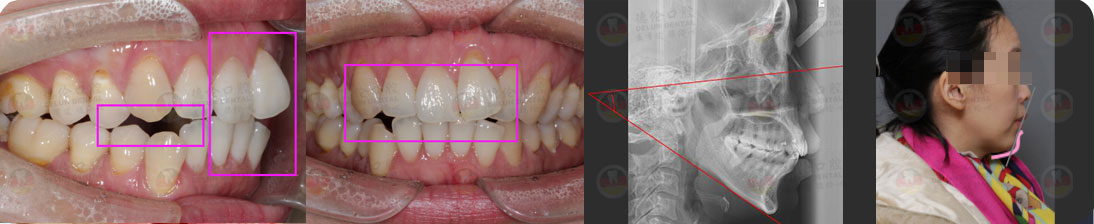

- 【診斷】

骨性I類,均角,安氏I類

上牙列重度擁擠,下牙列輕-中度擁擠

上中線右偏

13唇側(cè)錯(cuò)位

- 【治療方案】

拔除14,排齊上牙列

下頜尖牙適當(dāng)擴(kuò)弓,配合適量鄰面去釉,排齊下牙列

上頜左側(cè)配合適量鄰面去釉,調(diào)整中線

盡量調(diào)整后牙為尖窩咬合關(guān)系

矯治前后對(duì)比

蛻變周期:上頜16個(gè)月,矯治效率提升30%,下頜12個(gè)月,矯治效率提升20%